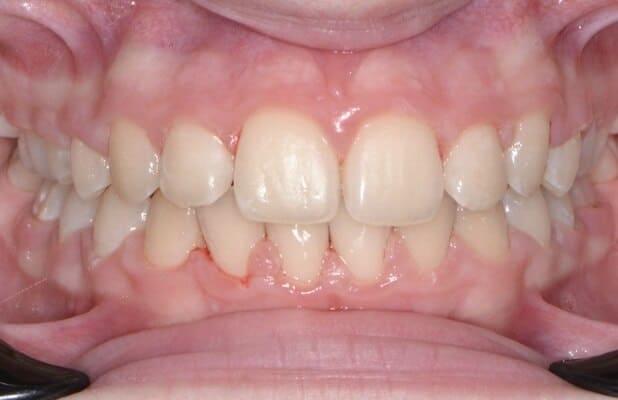

Маленька дівчинка двох років. Лікування проводилось в умовах анестезіологічного забезпечення. Завдяки злагодженій команді анестезіологічної та стоматологічної команди було проведено складне та об’ємне лікування. Було проведено лікування карієсу, герметизація фігур та лікування пульпіту (запалення «нерва») передніх зубчиків з відновленням естетичними коронками. Також бічні зубчики відновлені коронками металевими. Коронки можна комбінувати: на бічні ділянки встановлювати металеві, а на передні зубчики естетичні, щоб забезпечити оптимальну функцію та естетику.